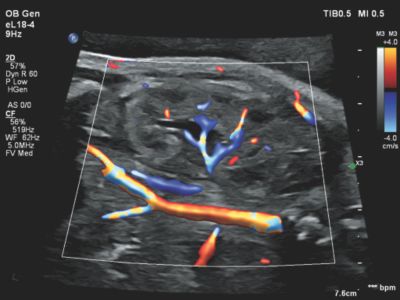

Flow Viewer applied to color flow with eL18-4 fetal kidney

Remarkable dimensionality in color modes with Flow Viewer

Flow Viewer provides a “3D-like” rendering on every color mode used for flow imaging data (Color, CPA/CPAd, MFI, and MFI HD) to help better visualize fetal vessels and fetal heart structures.

The 3D appearance has its advantages in clarity and boundary definition over traditional color flow for vessel and fetal cardiac identification.